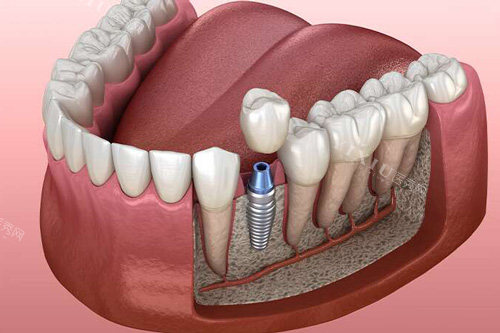

种植修复类

进口种植牙(含种植体+基台+冠):5200元起

瑞士ITI种植系统:12800元起

韩国奥齿泰种植系统:6800元起

全口半固定种植修复:38000元起

即刻种植牙(单颗):8800元起